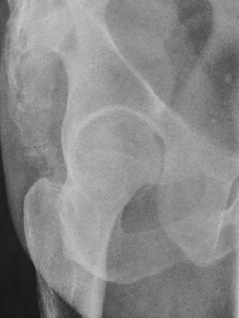

• For femoral neck, flex affected knee and hip, and abduct femur 45° from vertical (places femoral neck near parallel to IR).

• For femoral head, acetabulum, and proximal femoral shaft, oblique patient 35°–45° toward affected side and abduct leg to tabletop if possible. Center hip and neck area to CR.